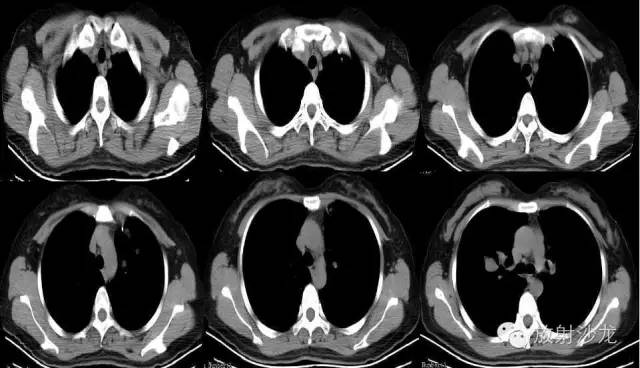

【影像表现】

双侧胸廓对称,纵隔居中。双肺可见散在多发大小不等类圆形软组织密度影,密度欠均,边界较清,最大者约5.32cm*7.88cm*6.75cm,右肺中叶、下叶可见一不规则形透亮影,内无肺纹理,纵隔未见明显肿大淋巴结,胸膜无增厚,右侧胸腔内可见弧形液体密度影。

右侧胸腔积液